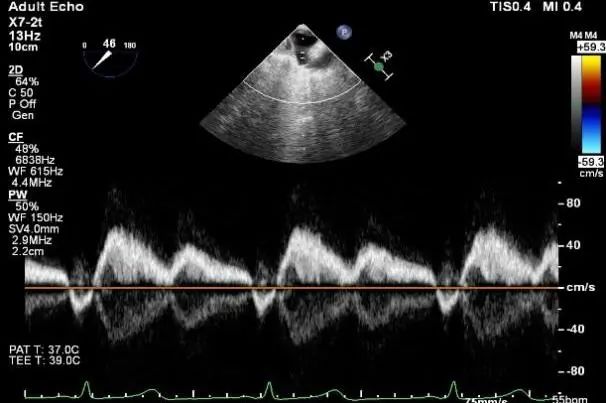

肺静脉多普勒收缩期反向血流

麻醉状态下TEE显示中大量返流MR:

术后肺静脉频谱

二尖瓣瓣口面积及平均跨瓣压差评估(4mmHg)